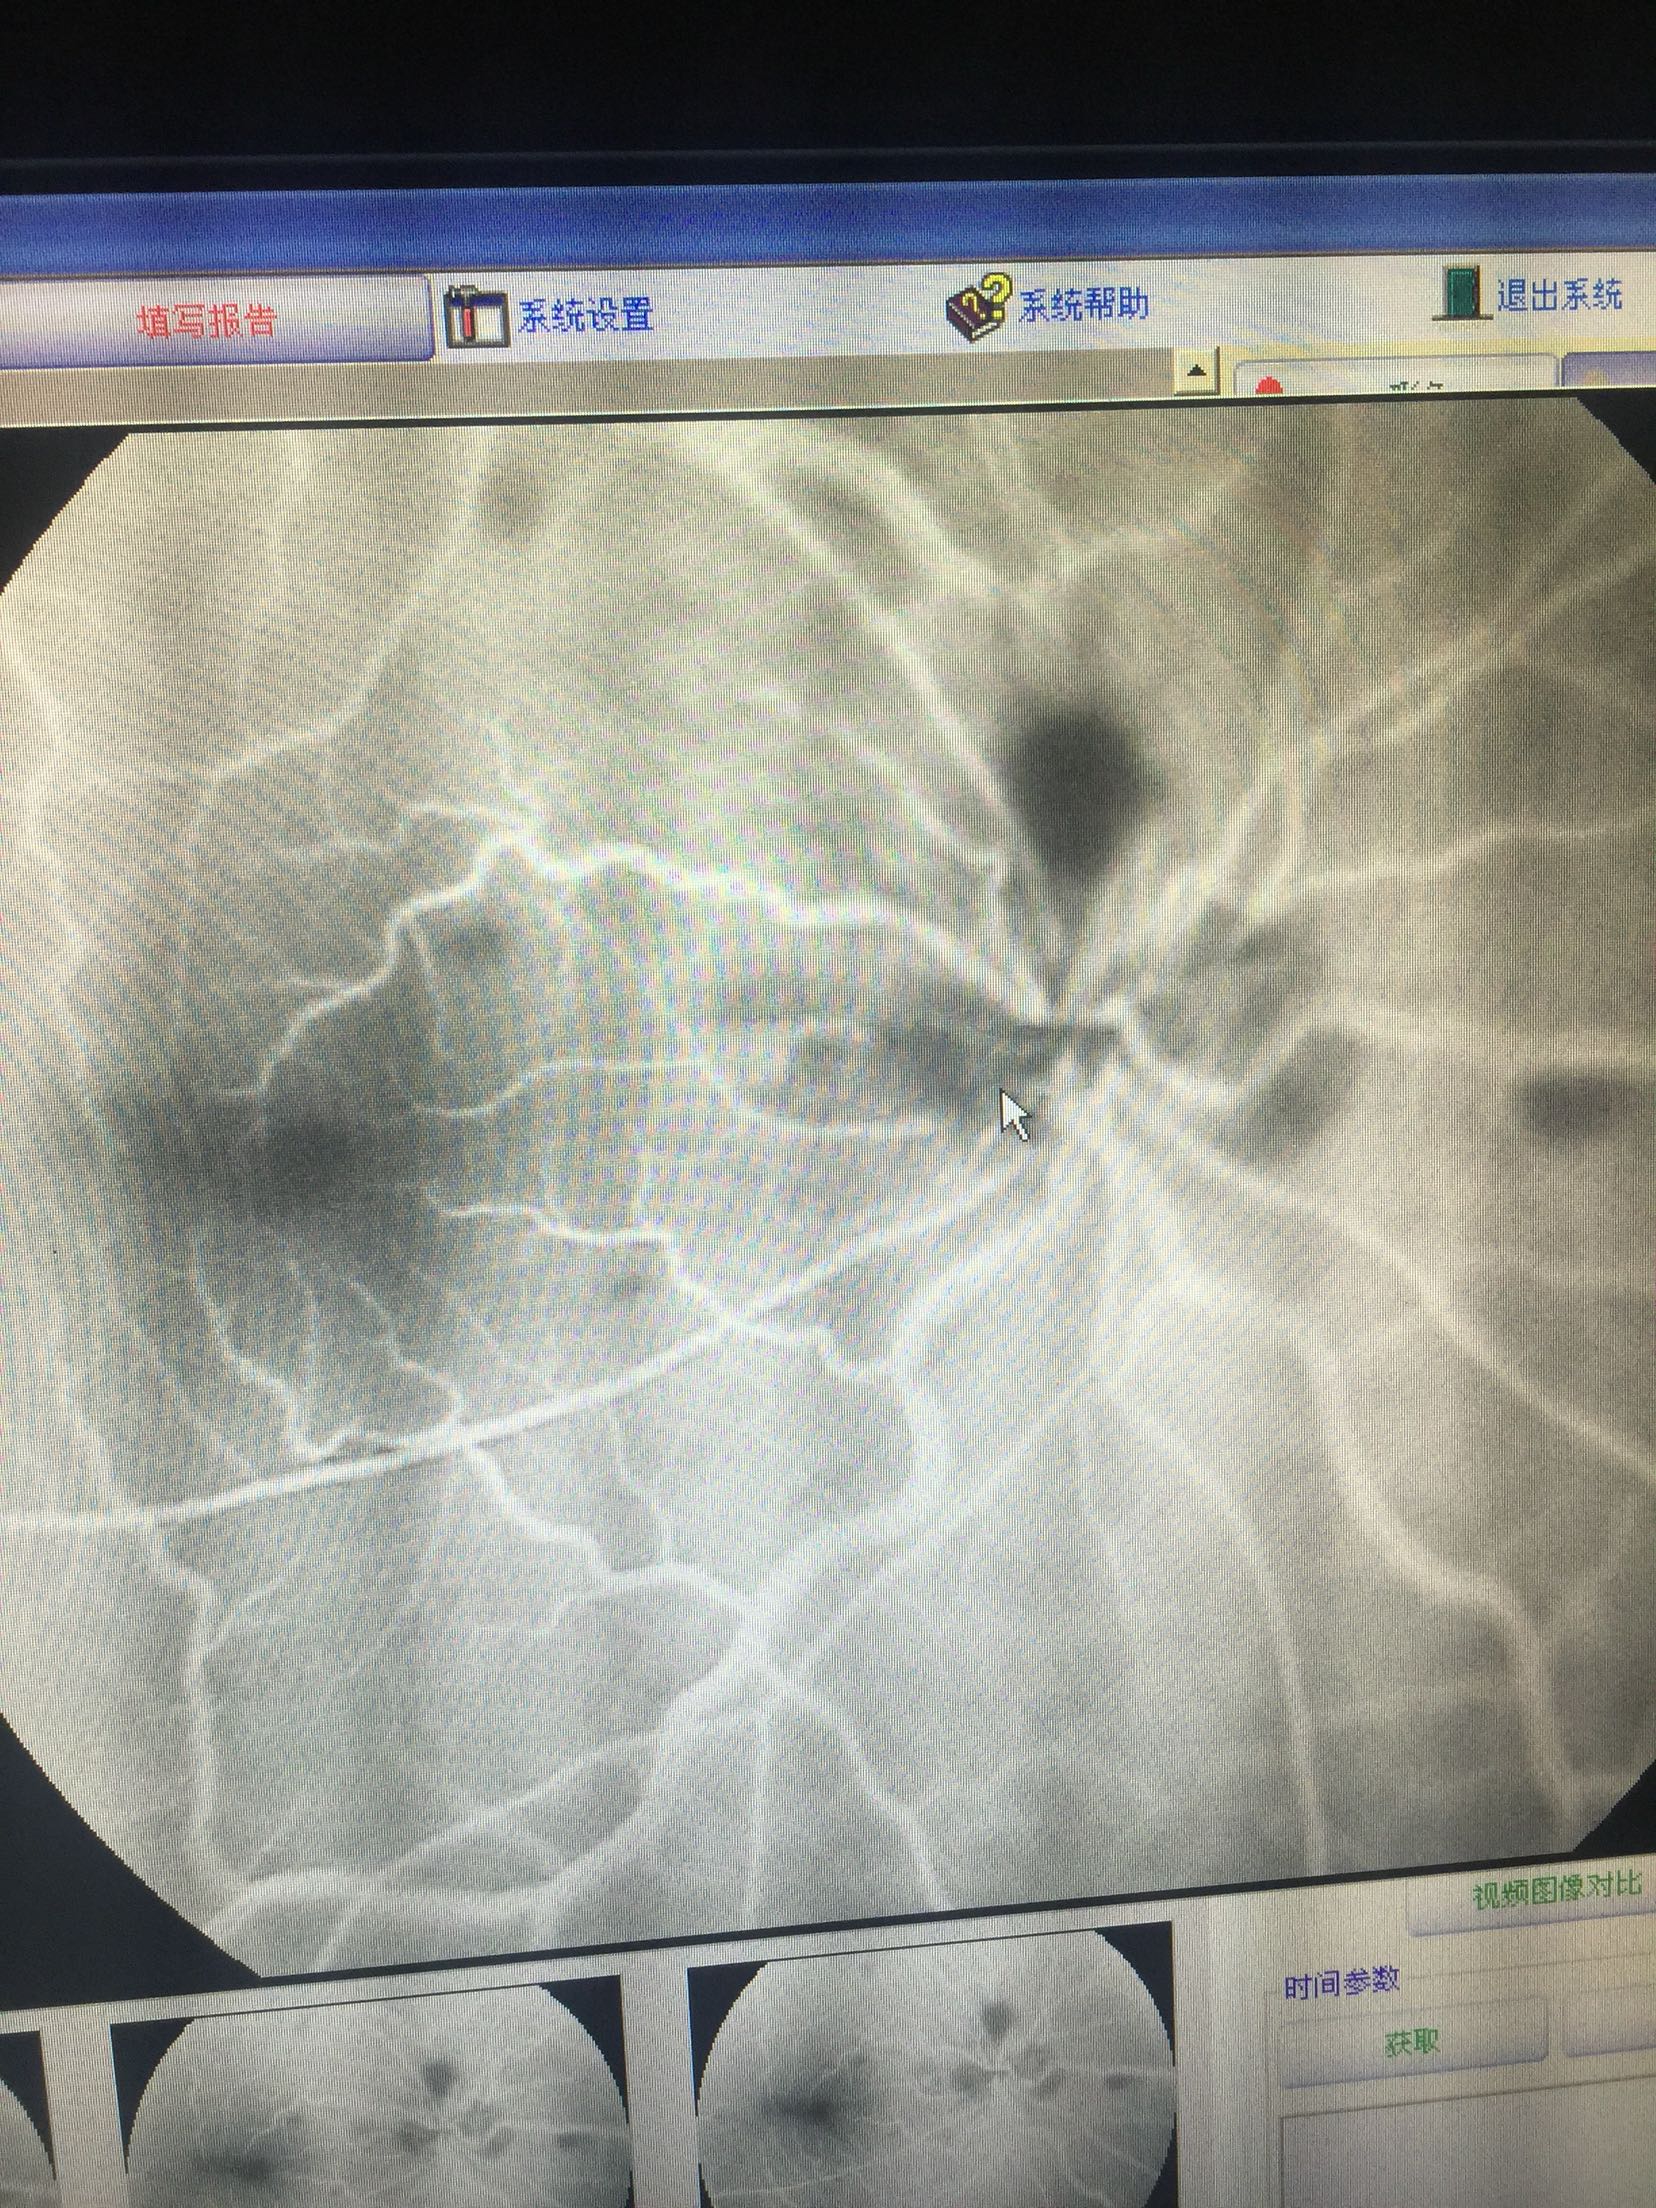

右眼:指数,左眼:0.15 双眼眼睑肤色正常,无红肿,结膜无充血,角膜透明,前房中深,瞳孔正大等圆,虹膜纹理清,晶体无浑浊,右眼眼底可见视盘出血水肿,边界不清,静脉迂曲扩张,黄斑区水肿出血,网膜散在片状出血,

右眼CRVO 扩张血管,营养神经治疗,眼底注射抗VEGF药

这种情况,很难有特别有效的预防手段,主要是规范生活习惯,避免劳累,饮食清淡。 眼底中央静脉阻塞引起的眼底出血,待出血吸收后,视力一般都会有进一步的提高的,但是要特别注意眼底新生血管增生的情况的,如果增生明显,会明显影响视力的,待出血吸收后,一定要做眼底造影明确的,必要时需要激光治疗的。